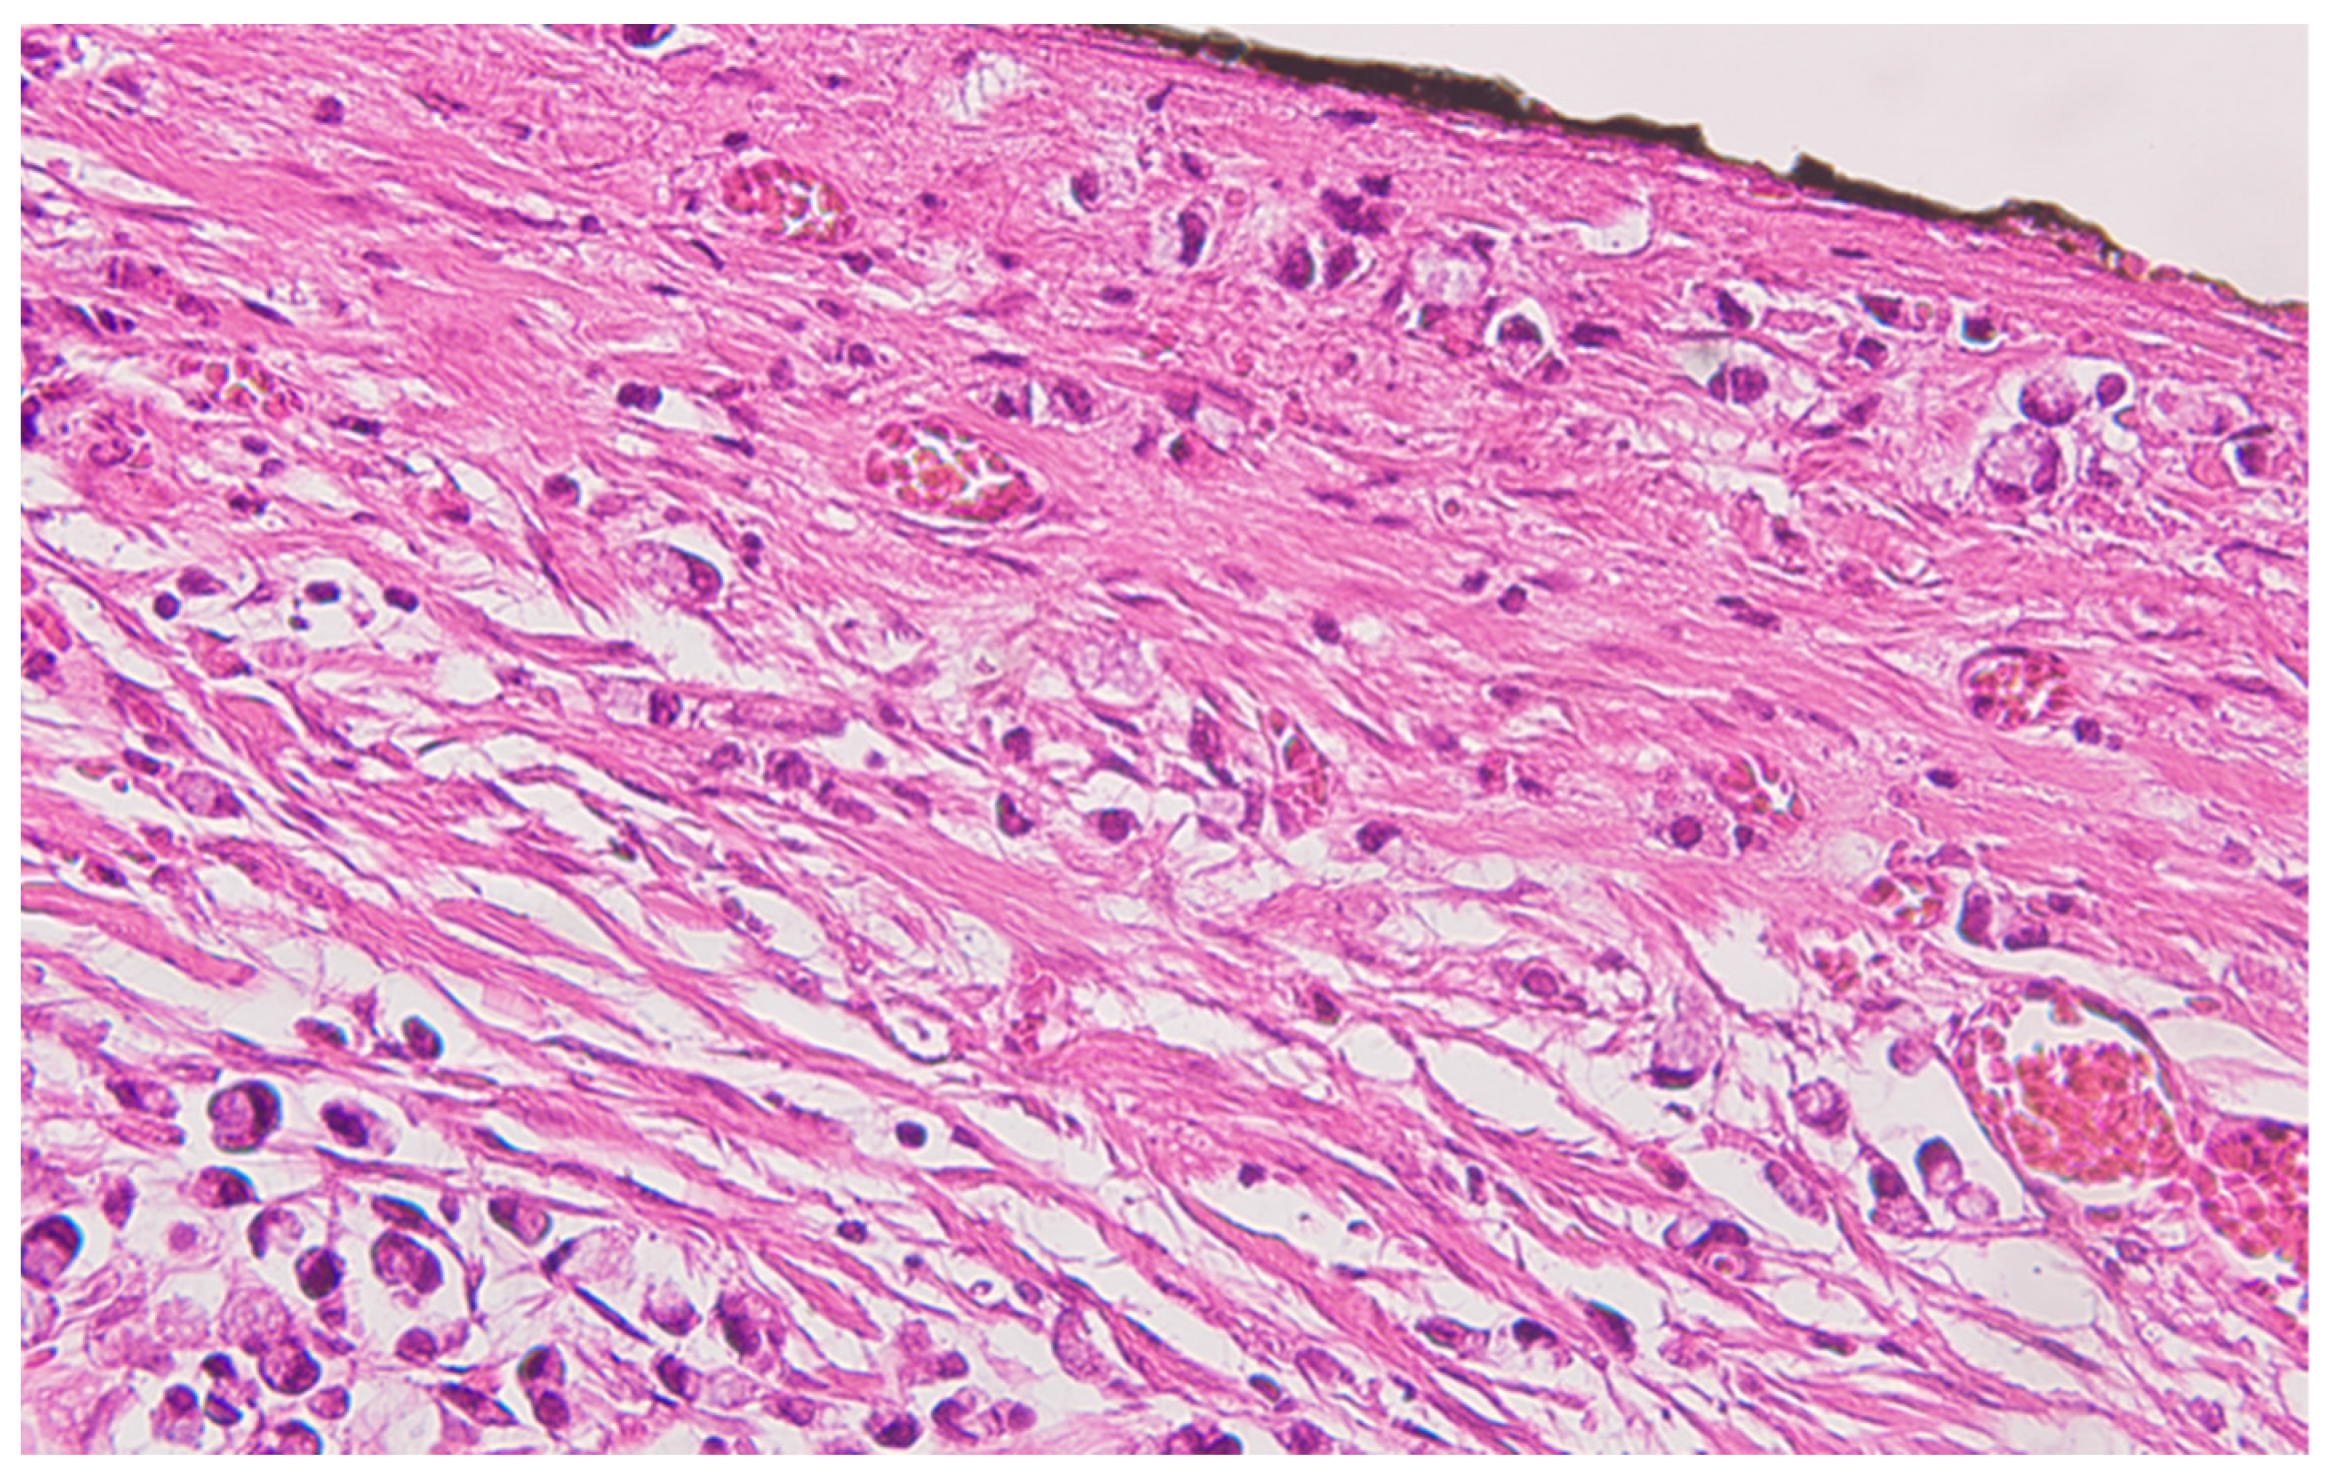

Serial sections of the ascending colon tumor reveal massive infiltration of a diffuse, mucinous carcinoma, with predominantly intracellular secretion of mucin (“signet-ring” cells); some isolated aspects of mucinous tubular adenocarcinoma are also observed. The tumor is ulcerated on the surface, extensively invades the submucosa (Figure 1), and dissociates the muscular layer (muscularis propria), being found massively in the subserosa (Figure 2), with perforation of the visceral peritoneum: tumor cells in ink or less than 1 mm from the inked serosa (pT4a); numerous lymphatic tumor emboli, with frequent aspects of perineural invasion. Of 26 lymph nodes, 24 show massive carcinomatous metastases (adenocarcinoma type, Figure 3)—pN2b.

Figure 2.

Colon mucinous carcinoma, with presence of carcinomatous cells in the subserosa, tangentially to the black ink marking of the peritoneal lining, HE ×400.